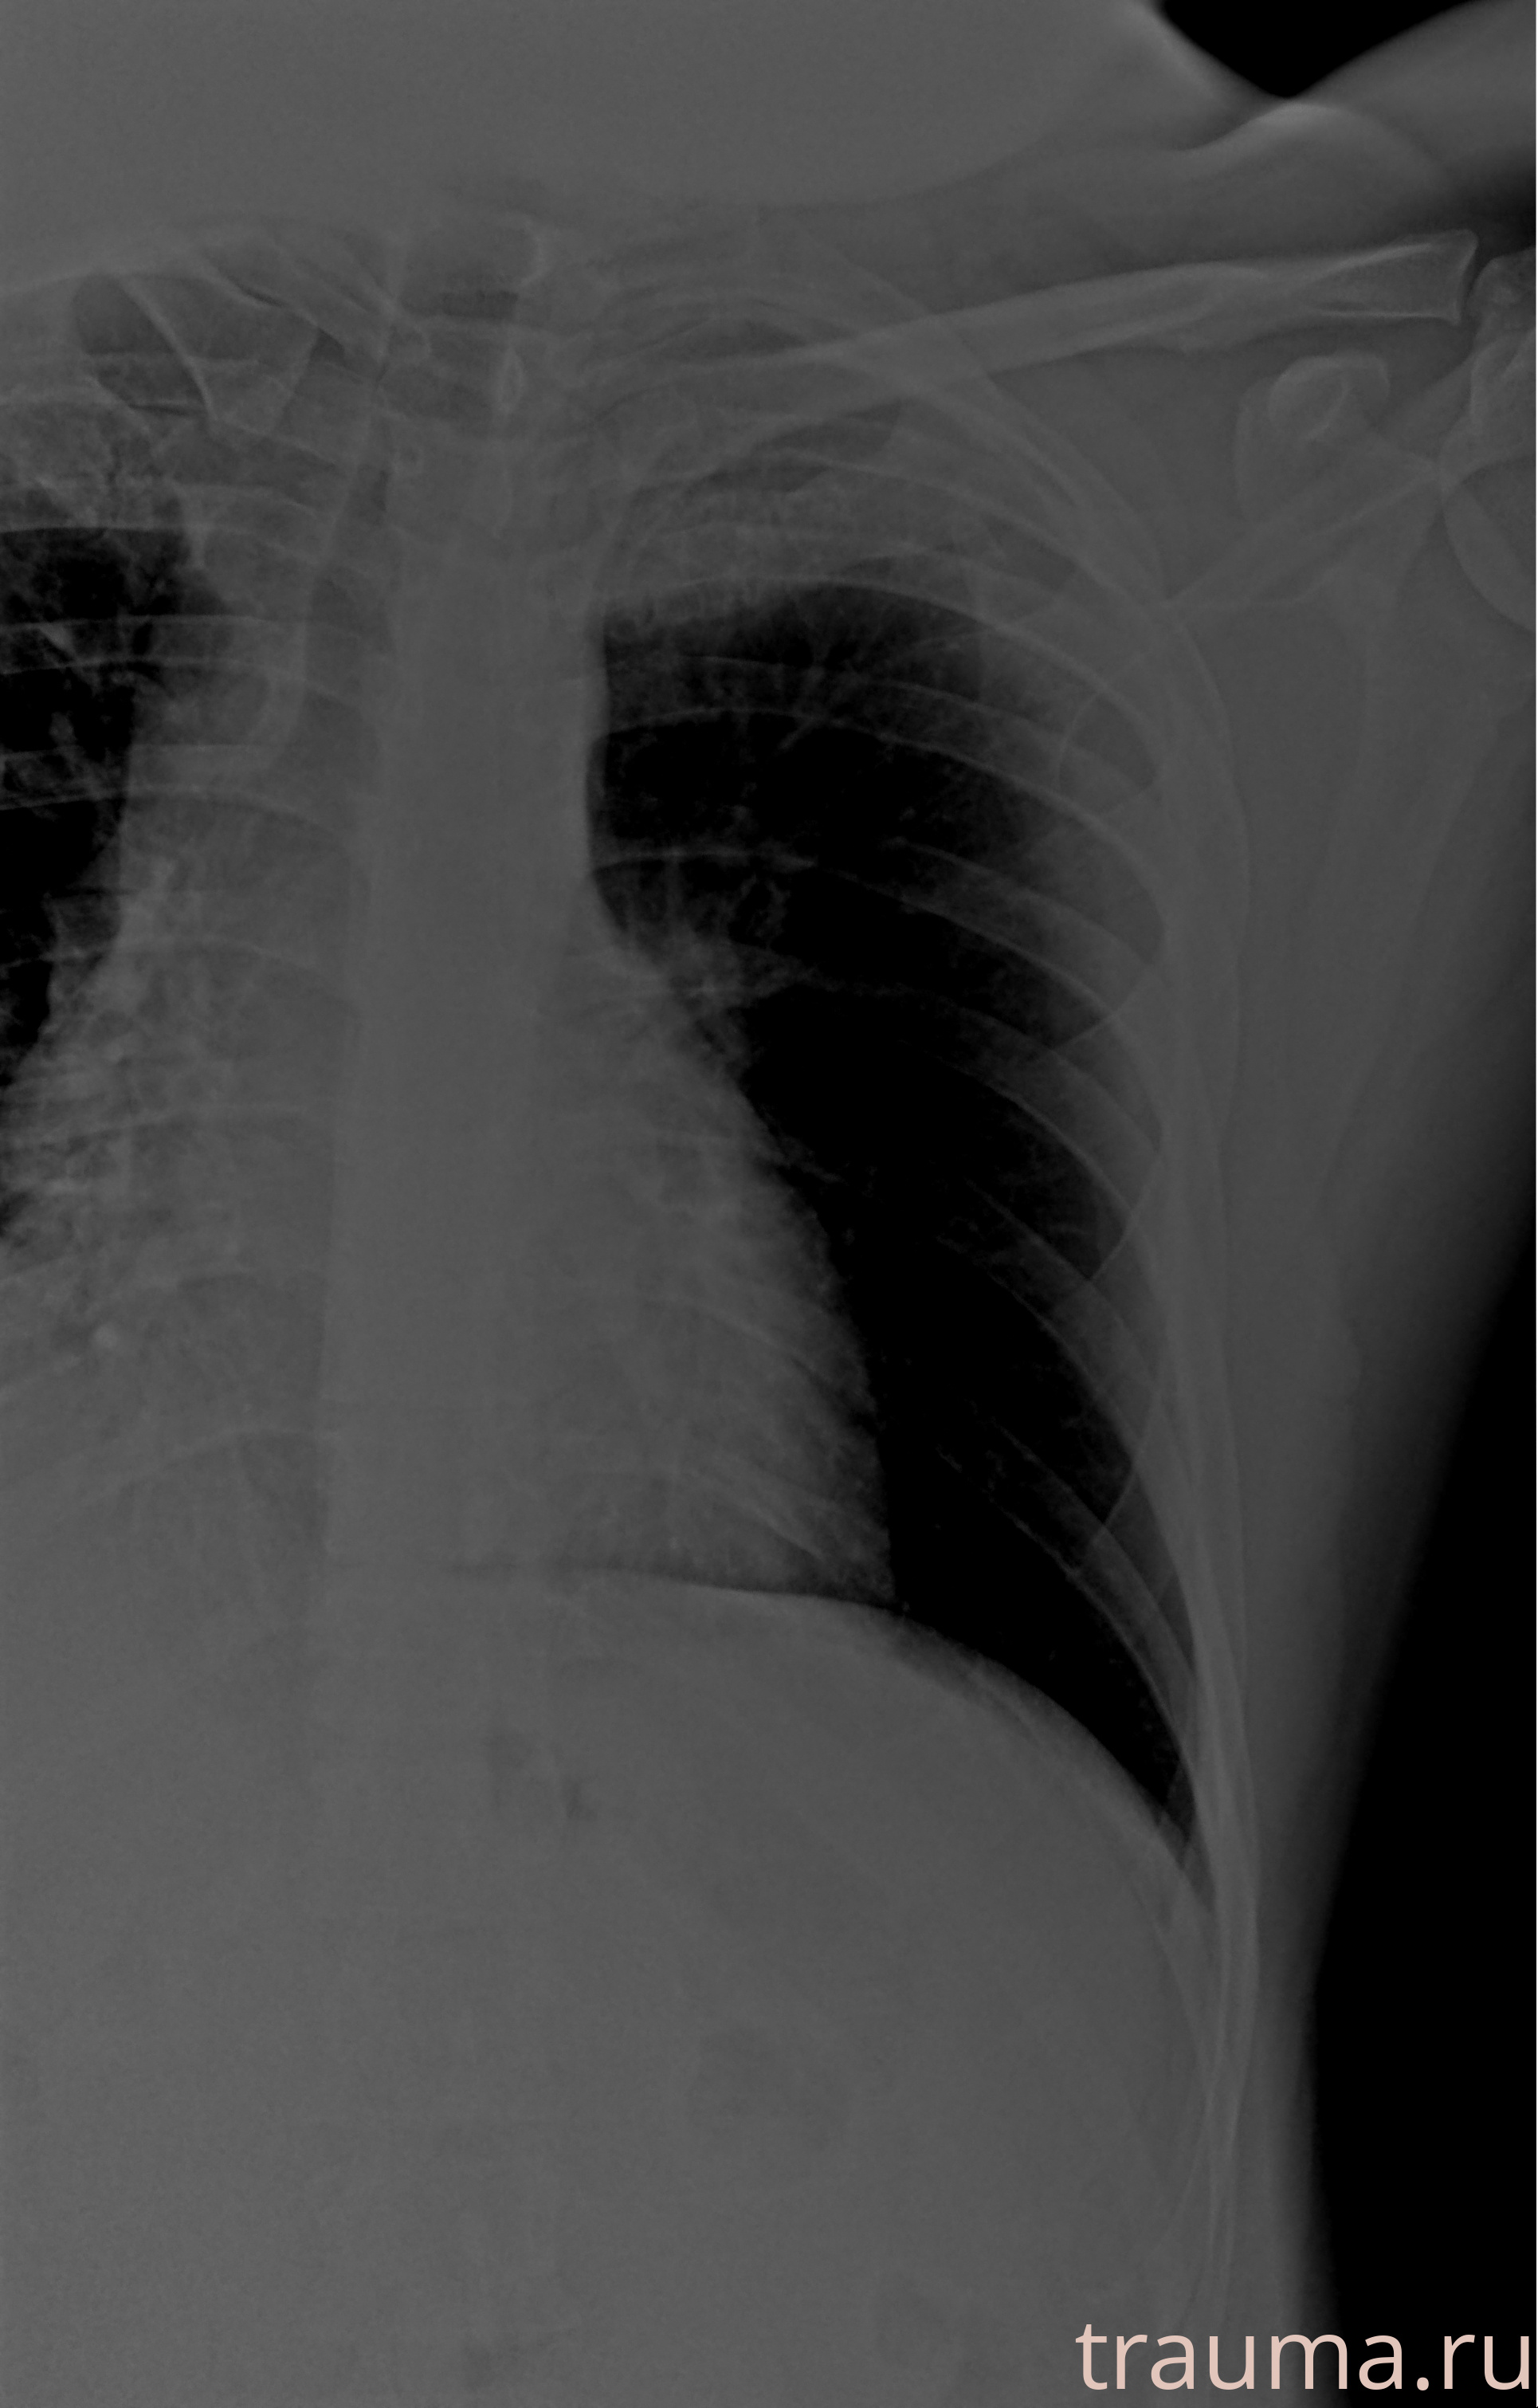

Рентгенограммы

Рентген на дому: по вашему адресу приезжает врач-рентгенолог, травматолог-ортопед с мобильным рентгеновским аппаратом, проводит диагностику травмы или заболевания, делает необходимые рентгенограммы, дает рекомендации по дальнейшему лечению. Получить качественные снимки в домашних условиях возможно благодаря уникальной методике, разработанной МосРентген Центром для института  Склифосовского

Яркость: 1   Контраст: 1   Инвертировать: 0 Увеличение: 1

Перетаскивайте мышь вверх/вниз для контраста, влево/право для яркости. Прокрутка колесом изменяет масштаб. Нажмите Сбросить для возврата к исходному изображению. При увеличении держите мышь в той области, которую хотите рассмотреть.